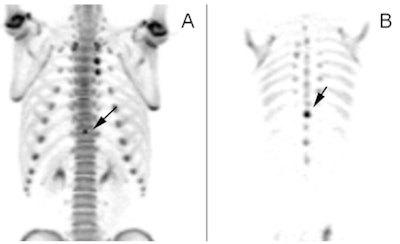

| Images of a 15-year-old male with mid and upper back pain show increased uptake in the spinous process (A) (arrow). The condition is confirmed on the coronal (B), sagittal (C), and transverse (D) images. |